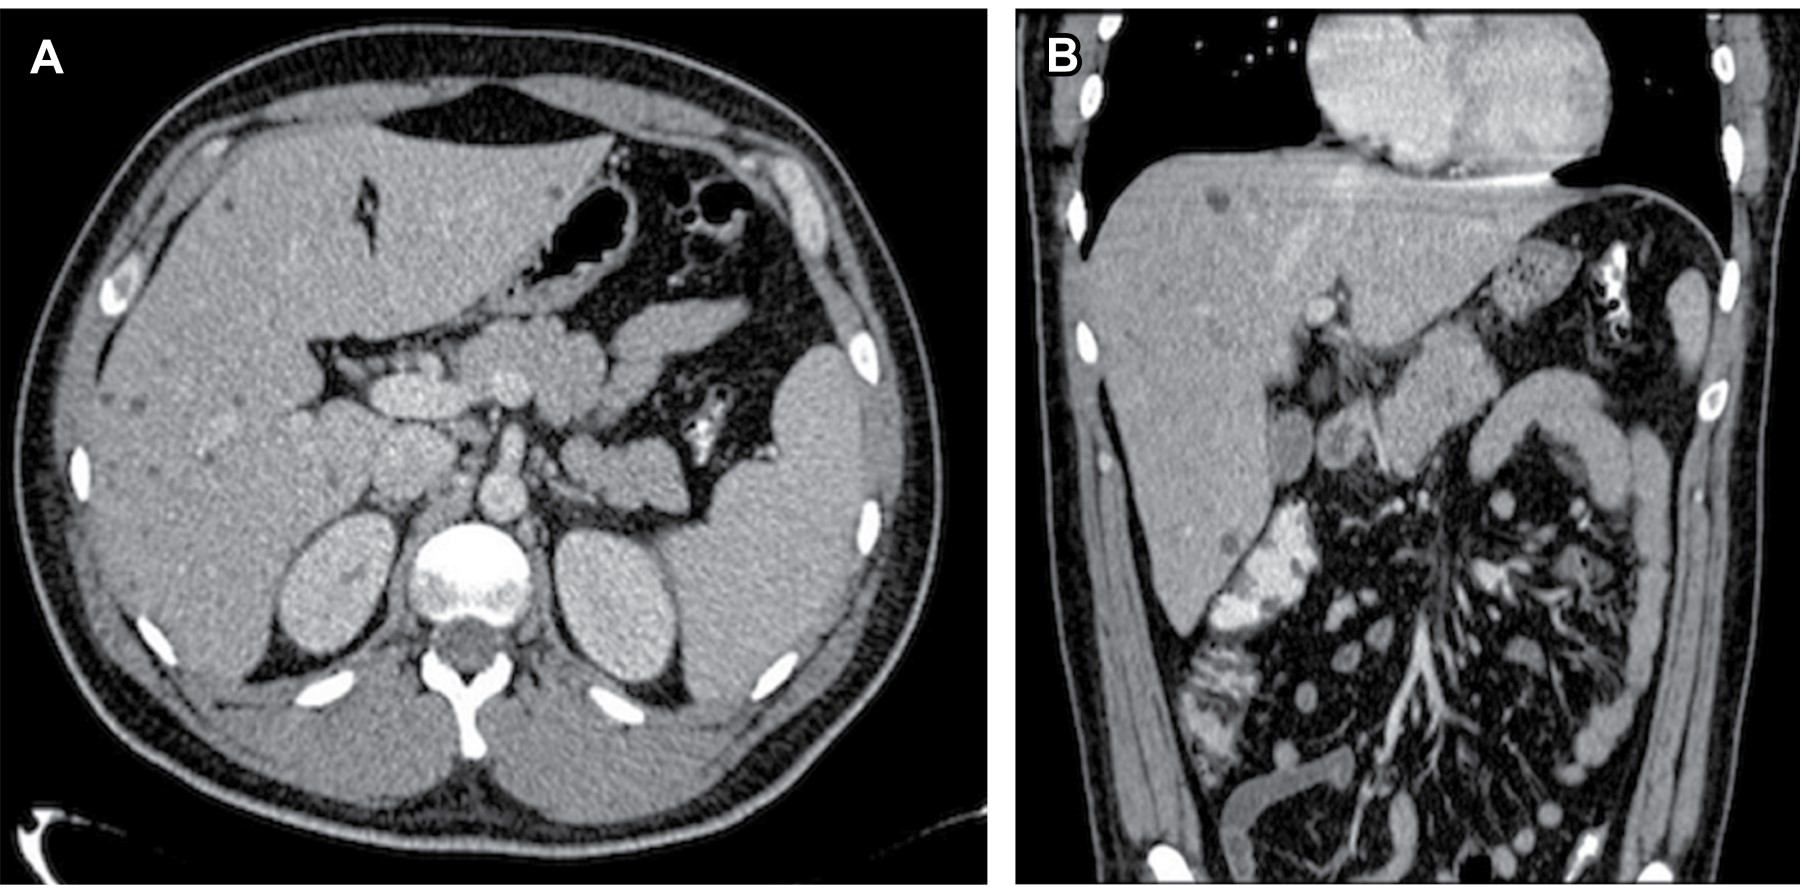

El diagnóstico por imagen se puede realizar por diversos estudios tales como ultrasonido y tomografía computarizada (TC); sin embargo, la colangiopancreatografía por resonancia magnética (MRPC, por sus siglas en inglés) es actualmente el método de elección debido a su elevada especificidad y sensibilidad.2,4 En estudios realizados con TC podemos observar la mencionada dilatación de los conductos biliares intrahepáticos como imágenes hipodensas, de bordes definidos y de densidad líquida, distribuidas de manera difusa o focal (Figura 1).1,2 Las imágenes obtenidas por medio de MRPC mostrarán múltiples lesiones de naturaleza quística de diversos tamaños que se comunican con el árbol biliar y que presentan una alta intensidad, al ser imágenes potenciadas en T2 (Figura 2).1,3

Figura 2